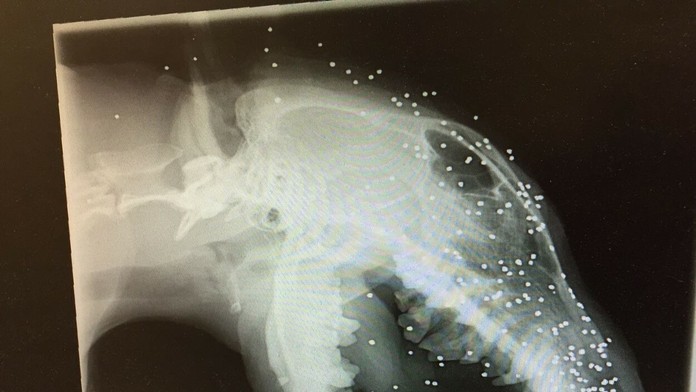

V Turecku strelili psíka do tváre brokovnicou, v lebke a koži má až 50 brokov

Anglického bulteriéra Erica strelili do tváre z bezprostrednej vzdialenosti, do hlavy sa mu zavŕtalo okolo 50 maličkých brokov.

Niektoré sa dokonca dostali až do jeho lebky. Hrozná udalosť sa stala v Turecku ešte v marci 2015, potom si ho adoptovala Britka Liz Haslam, ktorej nebol jeho osud ľahostajný a psíka sa snažila za každú cenu aspoň v rámci možností vyliečiť. Pani Haslam prevádzkuje útulok pre týraných psov.

Otrasné na celej veci je, že ani ona o guľkách v tele psa nevedela. Ericovi však opuchlo ucho a musel ísť na röntgen a ten odhalil šokujúcu pravdu o jeho stave. Lekári aj pani Liz zostali v úplne šoku. Na snímke sa objavili desiatky maličkých brokov.

Vedeli, že Eric je takmer slepý, no až teraz pochopili, že to spôsobil výbuch. Nakoniec sa ukázalo, že opuch ucha spôsobil zub iného psa, vrastený do Ericových úst. Fotografie ukazujú jeho úbohý stav.

Keď objavili guľky, veterinári jej povedali, že s tým sa nedá už nič robiť a pes s nimi aj zomrie. Podarilo sa im odstrániť aspoň vrastený zub, čo pani Liz stálo 800 eur.